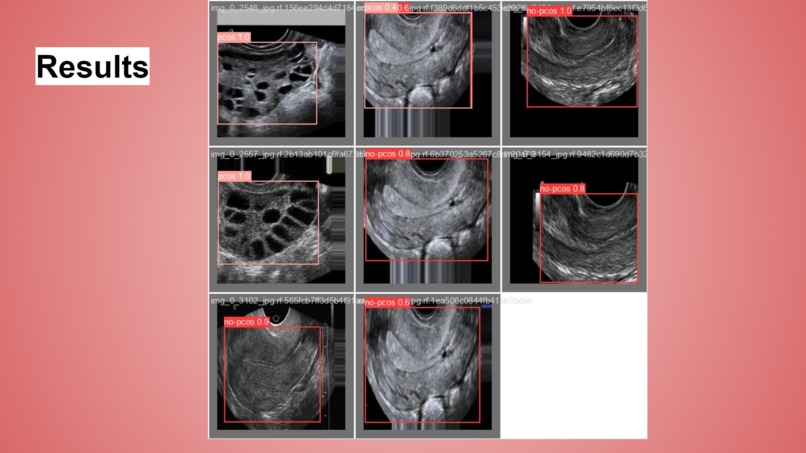

FemOvaAI is an advanced AI-driven system designed to detect Polycystic Ovarian Syndrome (PCOS) from ultrasound images. Utilizing the power of YOLOv8, a cutting-edge object detection model, our system analyzes images to classify them into two categories: "PCOS" and "No PCOS." This enables healthcare professionals to make informed decisions quickly, enhancing the diagnostic process and potentially improving patient outcomes.

Data Collection and Preparation: We used a publicly available dataset mentioned above containing 234 ultrasound images with 1363 labels, images are labeled into two classes: "PCOS" and "No PCOS." The dataset was split into training and testing sets to ensure robust model evaluation.

Evaluation and Testing: After training, the model was evaluated on the test set to assess its accuracy, precision, recall, and overall performance. Fine-tuning was performed to optimize the model further. Achieved a test accuracy of 92.9%.